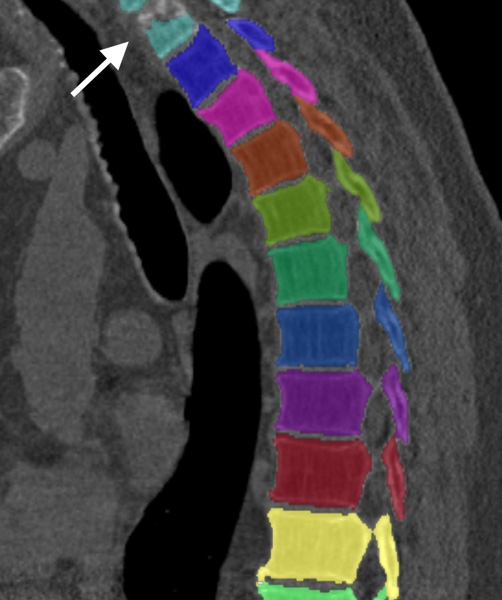

We trained and evaluated the method with five sets of CT and MR scans that visualize the spine. Reference segmentation masks for four of these datasets are publicly available, which allowed for a comparison with other publications that used the same data. Examples of images from the datasets are shown in Figure 3.

Similar performance was achieved for vertebra segmentation in various CT datasets with an average Dice score of and for vertebral body segmentation in an MR dataset with an average Dice score of . Surface distances were lower on CT images compared to MR images ( vs. ), however, there were also fewer training scans available in the MR dataset. Figure 4 illustrates the magnitude of differences of the automatic segmentations from the ground truth segmentations.

(a) Low-dose chest CT

(b) Lumbar spine CT (xVertSeg.v1 dataset)

(c) Lumbar spine MR

In the CT datasets, the segmentation was more accurate on high-resolution dedicated spine scans of healthy subjects compared with low-dose low-resolution chest CT scans and scans of subjects with in some cases severe compression fractures. This is also visible in the segmentation performance stratified by vertebra (Figure 5). Segmentations were more accurate for the lumbar (L1-L5) than for the thoracic vertebrae (T1-T12), which are covered by the more challenging low-dose chest CT scans. Outliers among the lumbar vertebrae correspond to vertebrae from the xVertSeg.v1 dataset, which features a number of severely deformed lumbar vertebrae that are particularly challenging to segment.